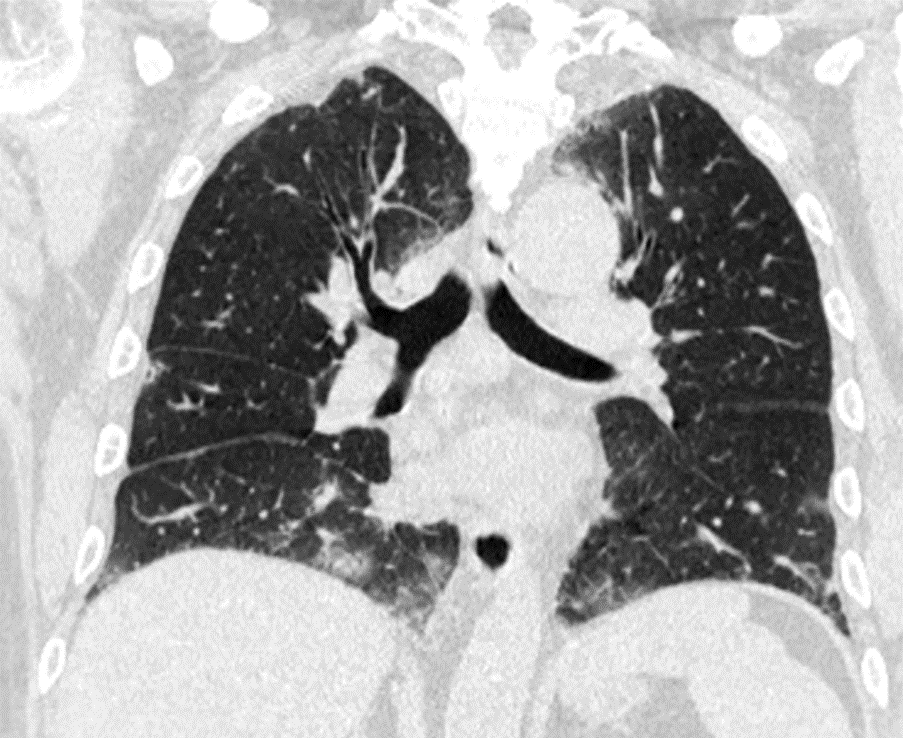

其实,这波omicron感染,确实肺炎比例比想象中要高,但很多都不会是大白肺,多数表现为双肺散发磨玻璃影,当然,也有单独的磨玻璃结节,特别容易表现为混合密度磨玻璃结节。其实很多新发的磨玻璃结节都是新冠肺炎,不用过于紧张,如果感染面积不大,一般临床上,也不需要特异性治疗,休息观察就行了。

可以考虑3个月以后复查一次薄层平扫CT。